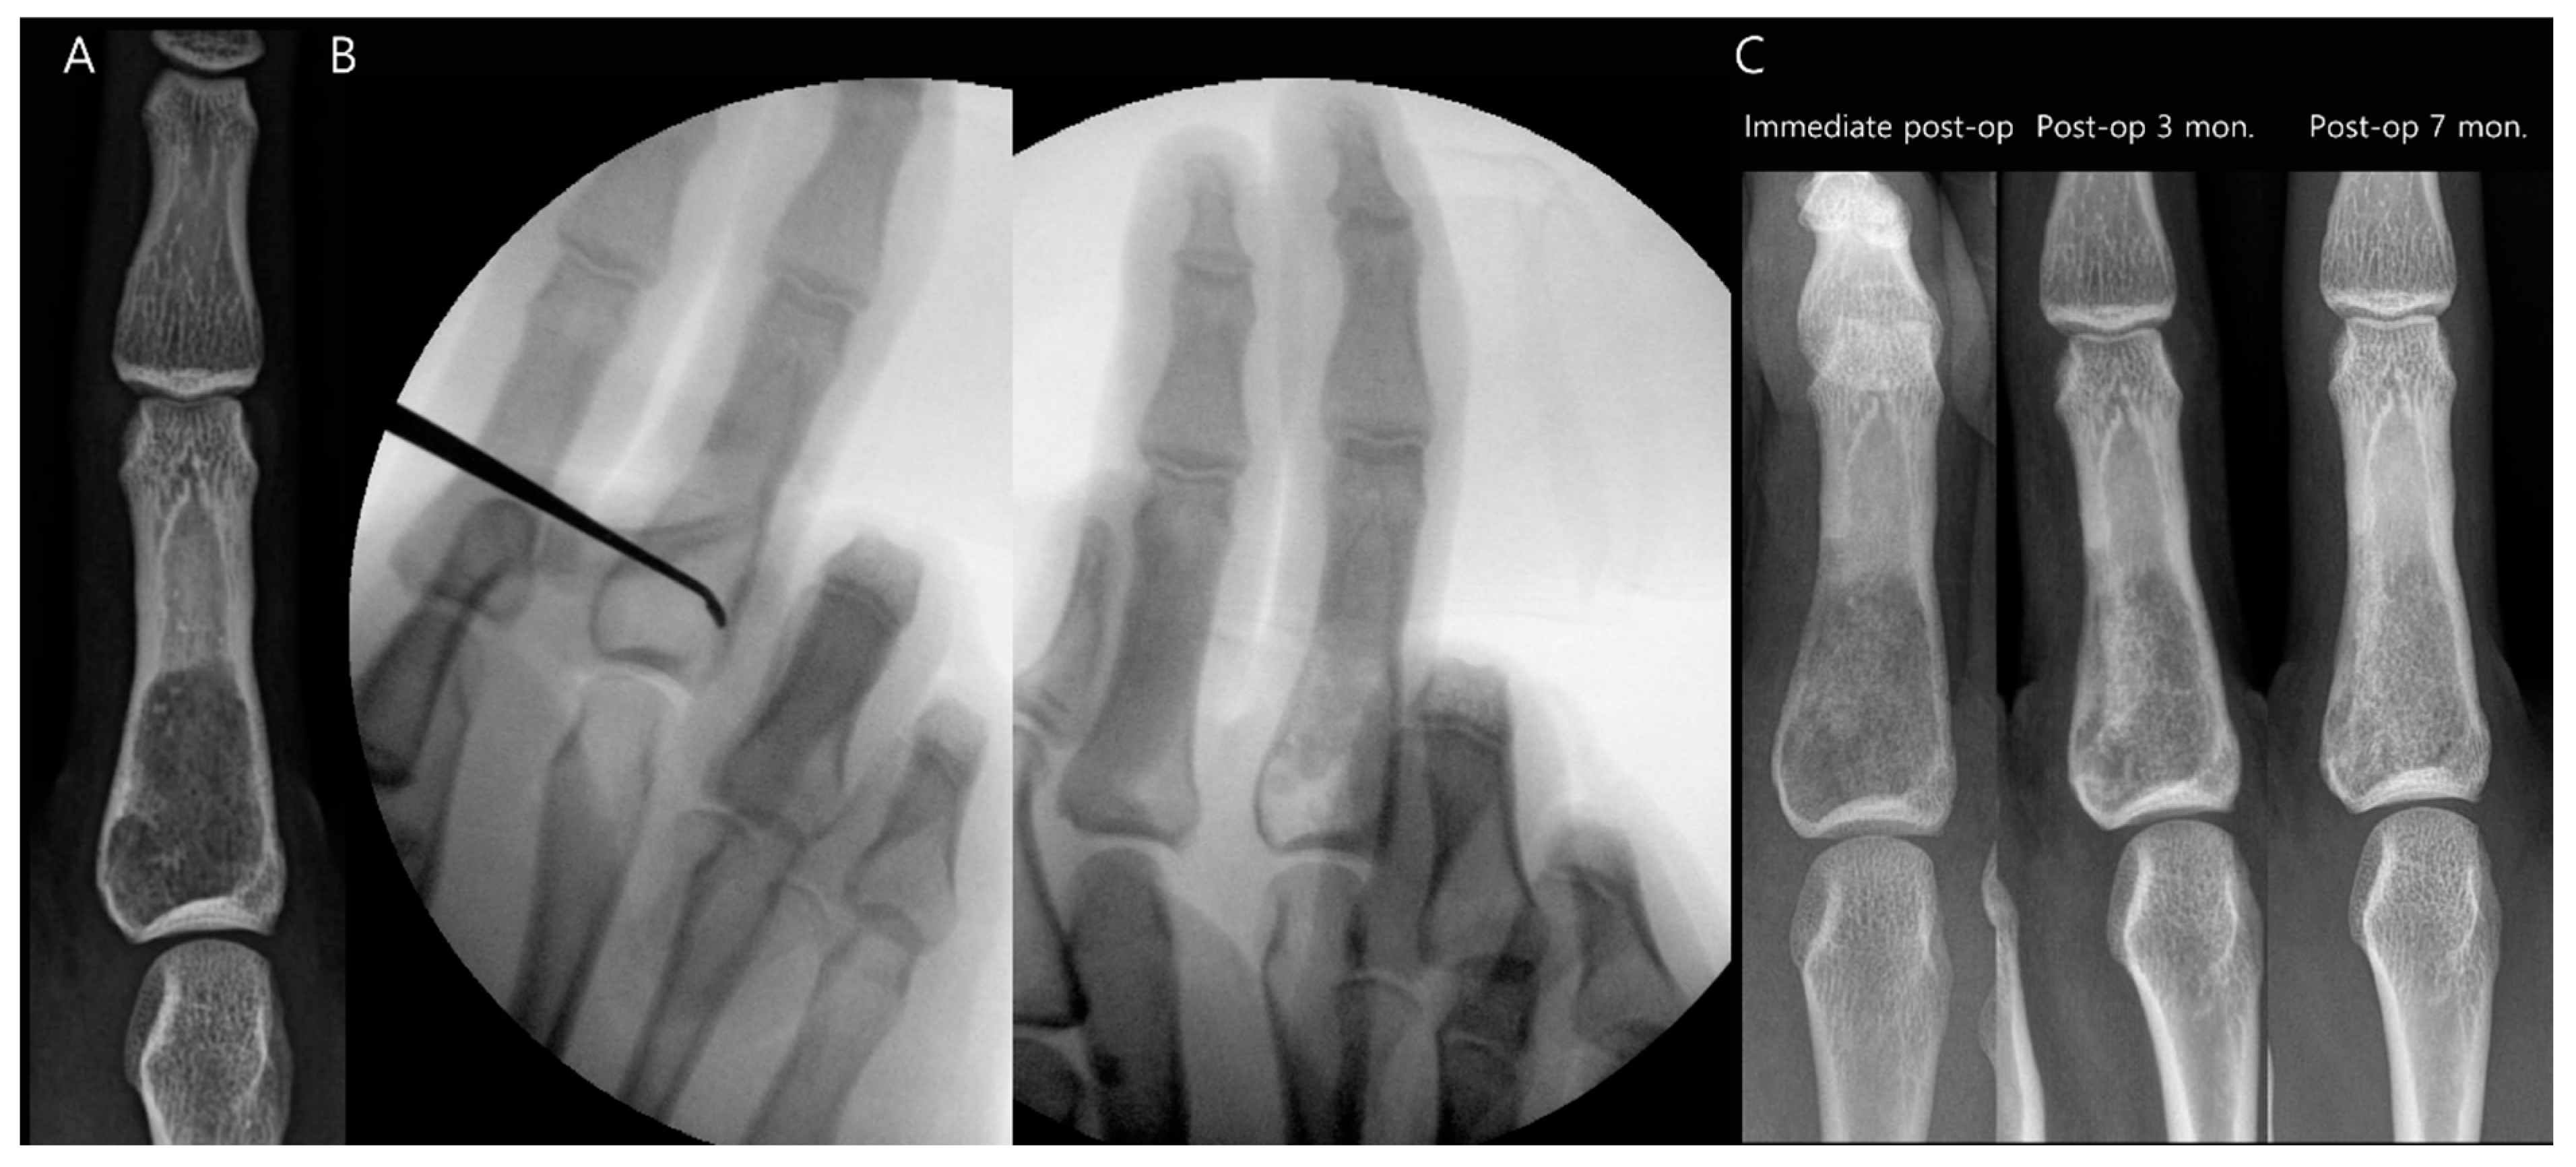

3.1. Bone Tumors

- Horstmann, P.F.; Hettwer, W.H.; Petersen, M.M. Treatment of benign and borderline bone tumors with combined curettage and bone defect reconstruction. J. Orthop. Surg. 2018, 26, 2309499018774929. [Google Scholar] [CrossRef] [PubMed]

- Lin, P.P.; Frink, S.J. Intralesional treatment of bone tumors. Oper. Tech. Orthop. 2004, 14, 251–258. [Google Scholar] [CrossRef]

- Komiya, S.; Inoue, A. Cementation in the treatment of giant cell tumor of bone. Arch. Orthop. Trauma Surg. 1993, 112, 51–55. [Google Scholar] [CrossRef]

- Wada, T.; Kaya, M.; Nagoya, S.; Kawaguchi, S.; Isu, K.; Yamashita, T.; Yamawaki, S.; Ishii, S. Complications associated with bone cementing for the treatment of giant cell tumors of bone. J. Orthop. Sci. 2002, 7, 194–198. [Google Scholar] [CrossRef]